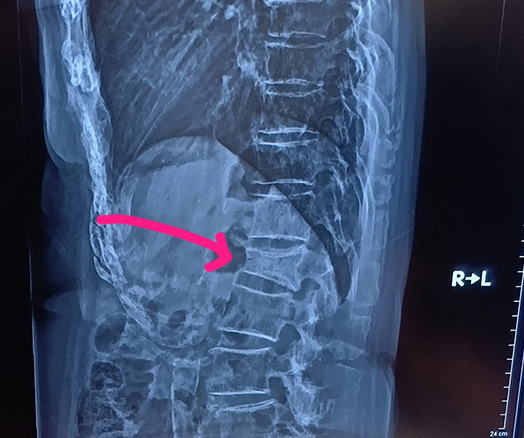

先週の土曜日ママリンはお家に帰っていきました~荷物一杯だったので弟に車で迎えに来てもらいましたw前回のレントゲンの結果 よくなってきてたのが見えたのであとは月一カルシウムの注射打つ時だけ うちに通ってくることになりました♪だいぶ一人でできるようになったしね♪これが先週のレントゲン矢印のところ見てこれが8月のレントゲンくっついてきてる感じ見えるよね♪ちょうど3か月たって ようやく治ってきた実感がわきました~♪でもまだ危ないのでコルセットはつけてるけどねw12月まではやってたほうがいいってお医者さんに言われたし~まあもう夏も終わりだから 汗だくにはならないと思う(笑)ではママリンとの先月最後のお祭り~天ぷら食べたい!っていうので うどん屋さんにしようとしてたけどだったら天丼やさんの方が絶対おいしいからってことで大海老天丼! 数量限定~~~♪海老天3尾だよwちょうど一人一本(* >ω<)=3 プー見切れてるのが旦那の~きつねうどんに かき揚げ♪前回私がきつねうどんにした時 おあげ気に入ったママリンのために~わたしはケンタでポテトとかフライドチキンもママリン好きだからシェア目的だよ~バーガーは野菜とソース増量にしたらこうなってたwマヨネーズ多めでたれはそのままの方がいいね(笑)

October 1, 2025